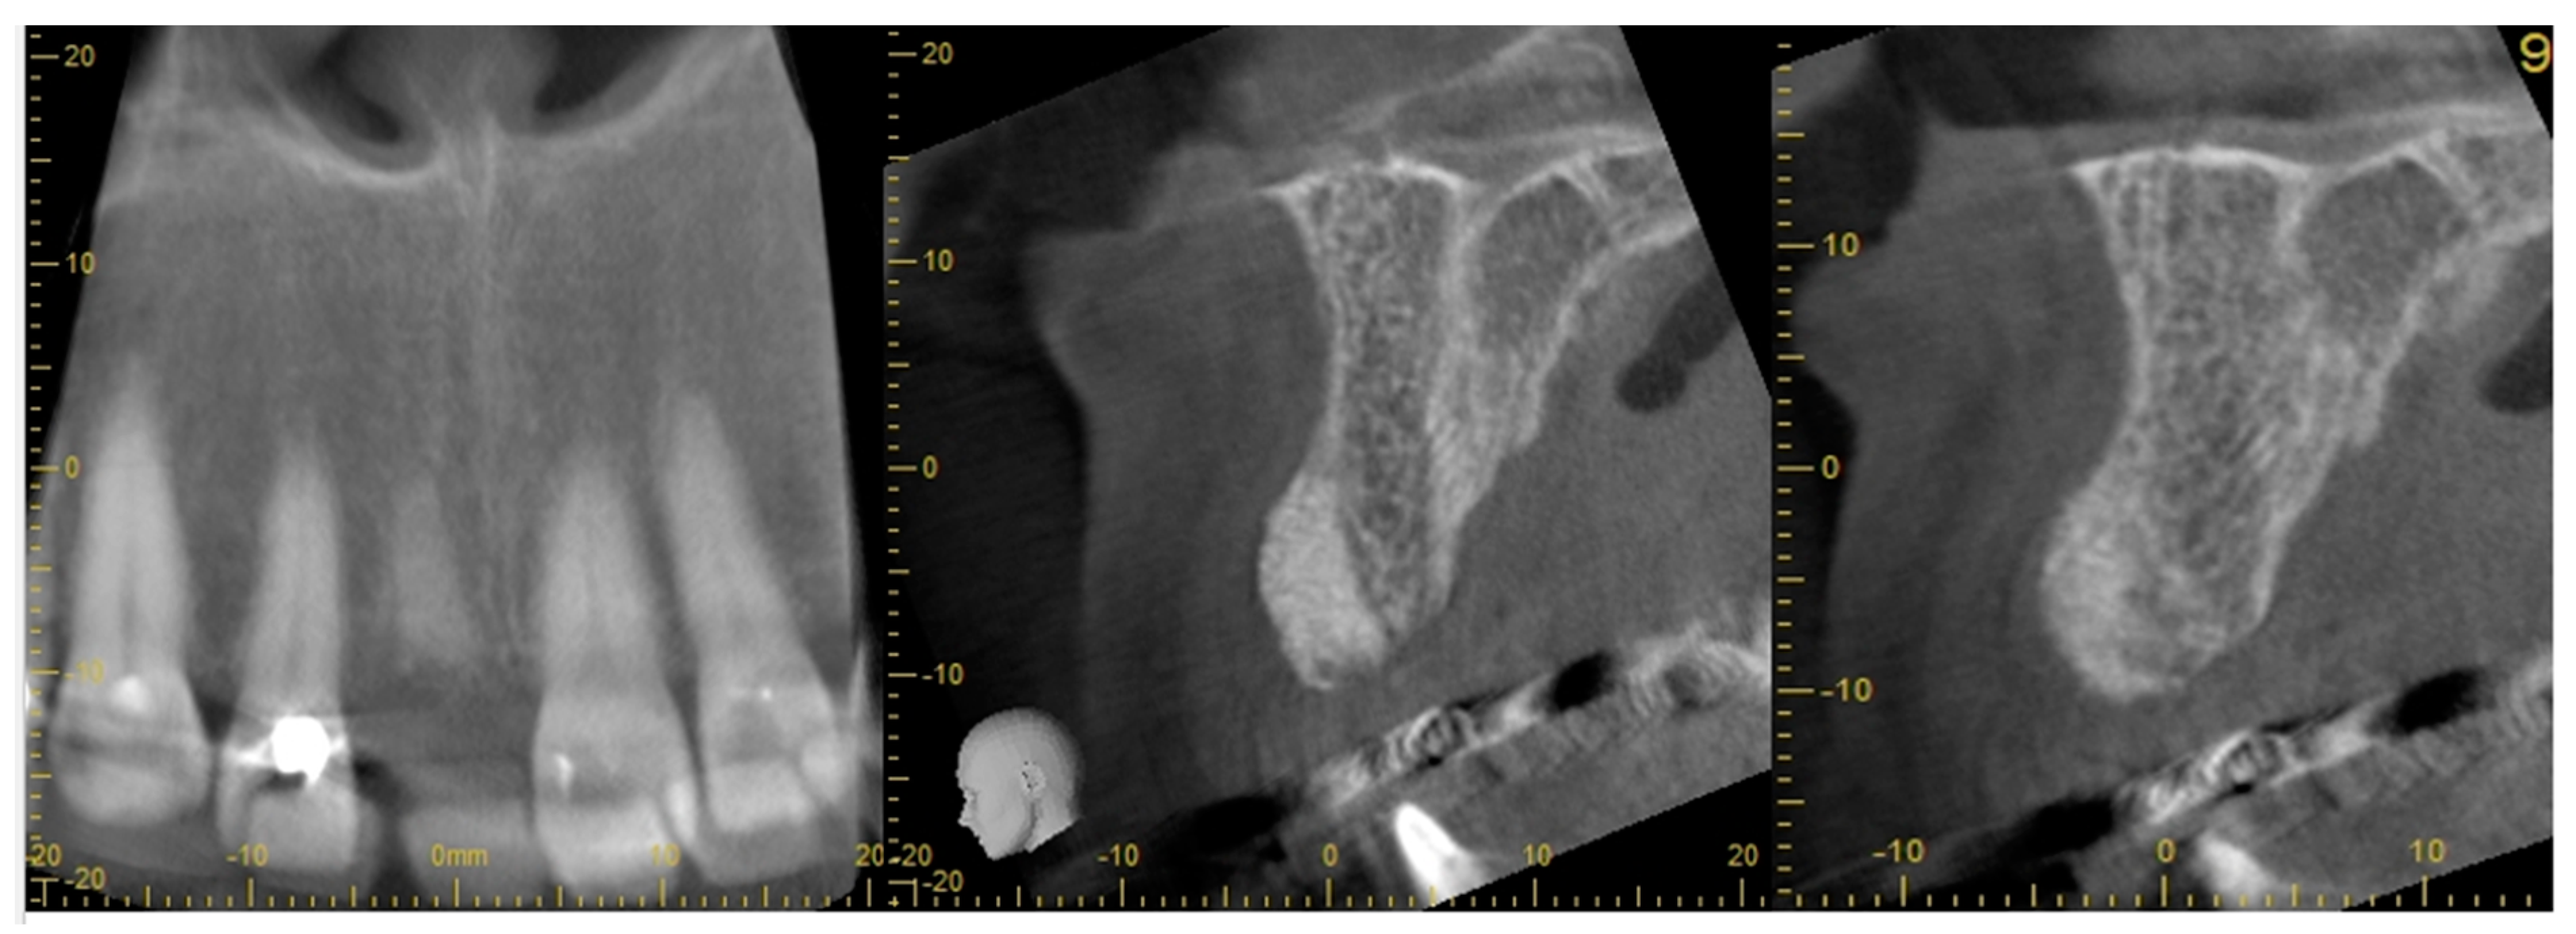

- Step 4: ARP graft healing was monitored radiologically. A CBCT was taken to plan for implant placement

- radiological assessment of bone quality and quantity after ARP using cone beam computerized tomography (CBCT)

- A CBCT scan of the sockets 8 weeks after ARP, before implant placement